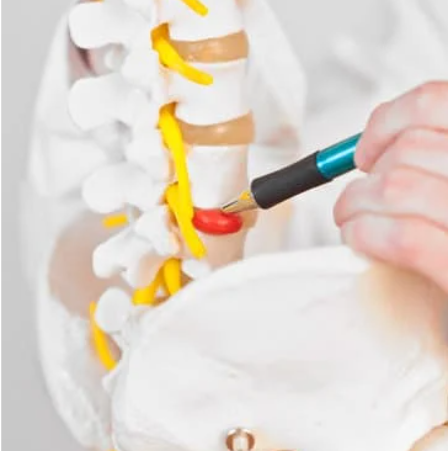

腰骨と腰骨の間には椎間板というクッションがあり、骨同士がぶつかるのを防いだり、腰骨を安定化させたりしています。しかし、時に椎間板の後ろに裂け目が入り、椎間板の中身(髄核)が後ろに飛び出し神経を圧迫し、腰痛や足のしびれ痛みを生じてしまうことがあります。これを腰椎椎間板ヘルニアと言います。ヘルニアは英語で飛び出すと言う意味なので、文字通り腰骨の椎間板が飛び出すことで起きる病気です。20-40歳の男性に多く、症状は様々で腰痛のみの場合や足のしびれ痛み(太ももの外側や後ろ側、ふくらはぎ)、さらにひどいと足の力が入らなくなったり、オシッコがでなくなったりすることもあります(この場合は緊急手術が必要)。症状が悪化する前に早期診断することが必要です。

まず診察を行います。腰や足のどの場所が痛いのかしびれるのかを確認します。またどのような姿勢で痛むのか、日常生活でどんな時がつらいのかを確認します。次にレントゲンのチェックをし、骨の異常がないかチェックします。ヘルニアを強く考える場合は、MRIを撮影し確定診断を行います。